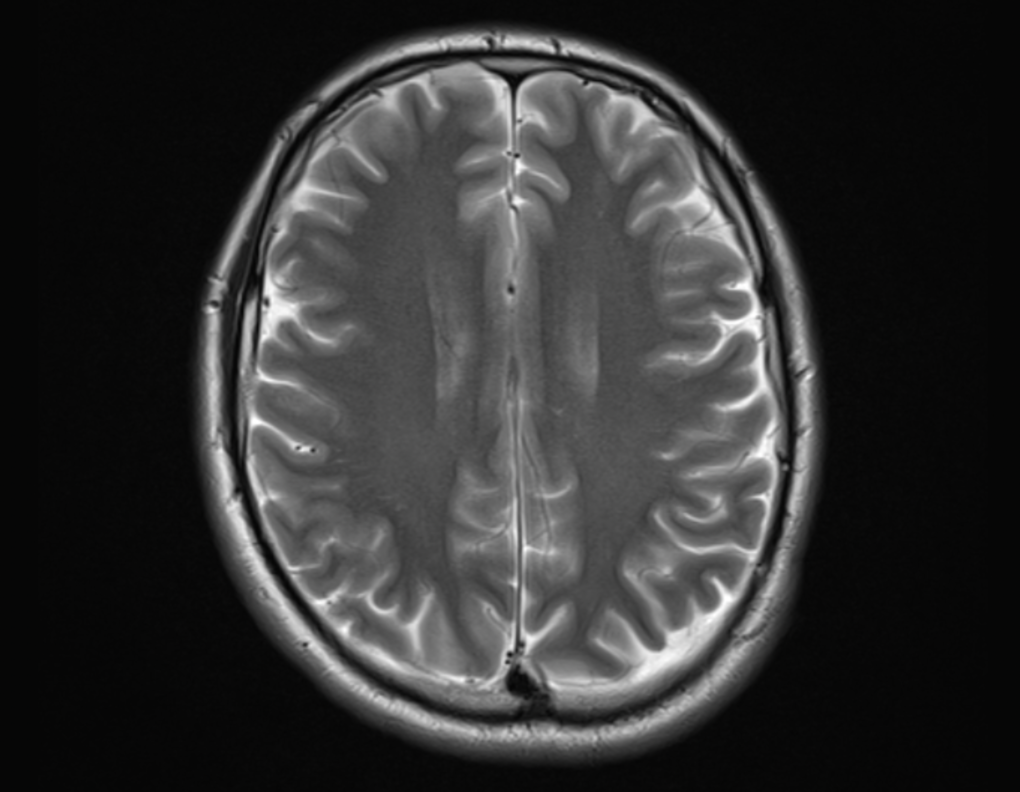

DICOM (Digital Imaging and Communications in Medicine) is a standard format that enables medical professionals to view, store, and share medical images irrespective of their geographic location or the devices they use, as long as those devices support the format. DICOM images need to be viewed through specific software called DICOM viewers that can read and display the format. The images, along with the corresponding patient data, are often stored in a large database called the Picture Archiving and Communication System (PACS). The purpose of a DICOM application is to store information in the PACS about the imaging examination, along with patient details, and then when required, to view and interpret (and possibly edit) medical images that are retrieved from the PACS. DICOM images are unique in the fact that they contain patient information in addition to the image data.

Most DICOM applications today read common imaging modalities like CT, MRI, and ultrasound images. Features such as multiplanar reconstruction (MPR), particularly 3D reconstruction, are needed for treatment planning. Volume rendering, maximum and minimum intensity projections (MIPs) aid in diagnosis as well as in research. Image fusion, such as PET to CTs or PET to MRIs can also help in diagnosis and reporting.